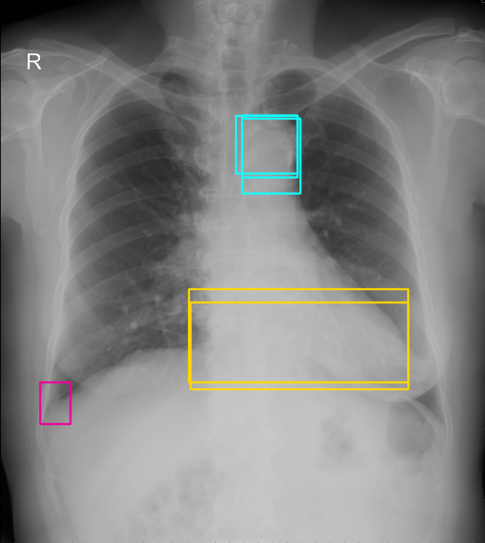

We firstly estimate the true labels using Weighted Boxes Fusion (WBF) algorithm [13]. This technique is used for combining predictions from multiple sources, i.e., using ensemble to achieve better prediction results or combining labels of different expert annotators. We describe the WBF algorithm in more detail in Algorithm 1. The final examples used to train deep learning detectors contain merged boxes with confidence scores. The visualization of fused boxes and the corresponding confidence scores are shown in Figure 2. Our fusion box algorithm emphasizes that the greater agreement between bounding boxes (e.g., two or three annotators have the same diagnosis for an abnormal finding on the image), the more likely the box annotation is correct.

Refer to caption

(a) The original annotations provided by multiple radiology experts. The same abnormal finding is represented by the sample color.

(b) Fused boxes with corresponding confidence scores after applied the WBF algorithm.

Figure 2: (a) Visualization of multiple expert annotations on a chest X-ray example from the VinDr-CXR dataset [5] and (b) the fused boxes with confidence scores obtained by the WBF algorithm.